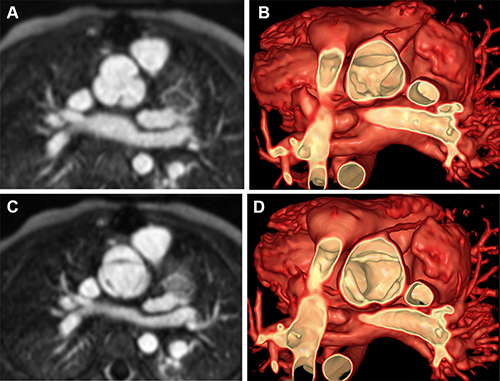

Figure 6. Visualization of neoaortic valve using ferumoxytol-enhanced multiphase steady-state imaging with contrast enhancement (ie, MUSIC) cardiac MRI in a 5-year-old female patient with neoaortic insufficiency (patient 4) to inform valve repair. (A) Axial view of volume rendering looking down at neoaortic valve. (B) Coronal view of volume rendering cutting through aortic valve. (C) Segmentation of neoaortic valve demonstrates central defect. (D) Overlay of segmented image within volume-rendered image.